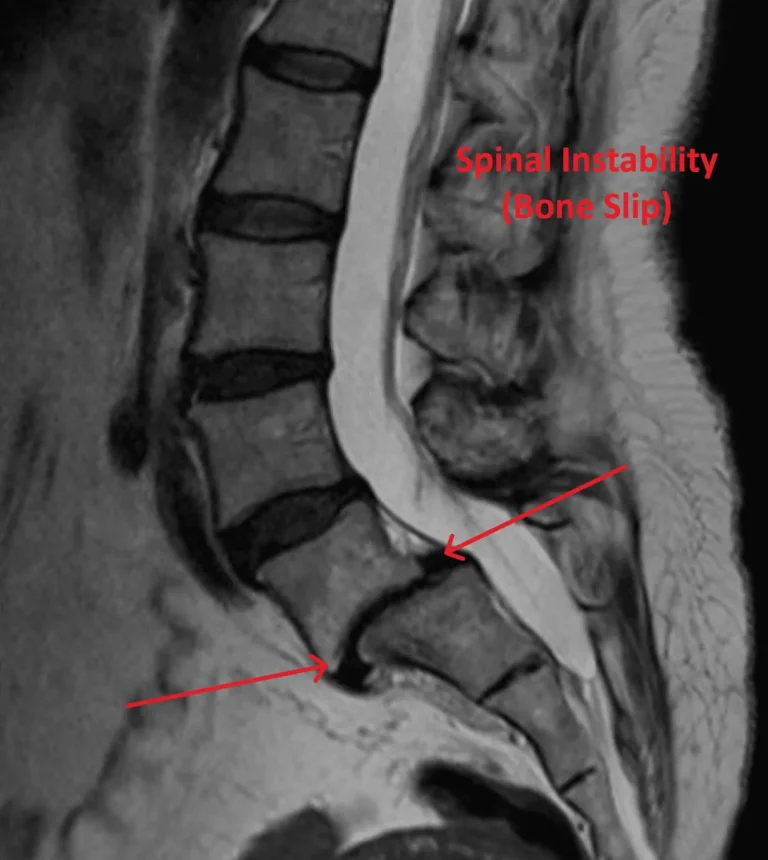

Spinal Instability After Fusion

X-rays of spinal surgeries showing metal screws and rods in the spine.

90%+ Need Additional Surgery